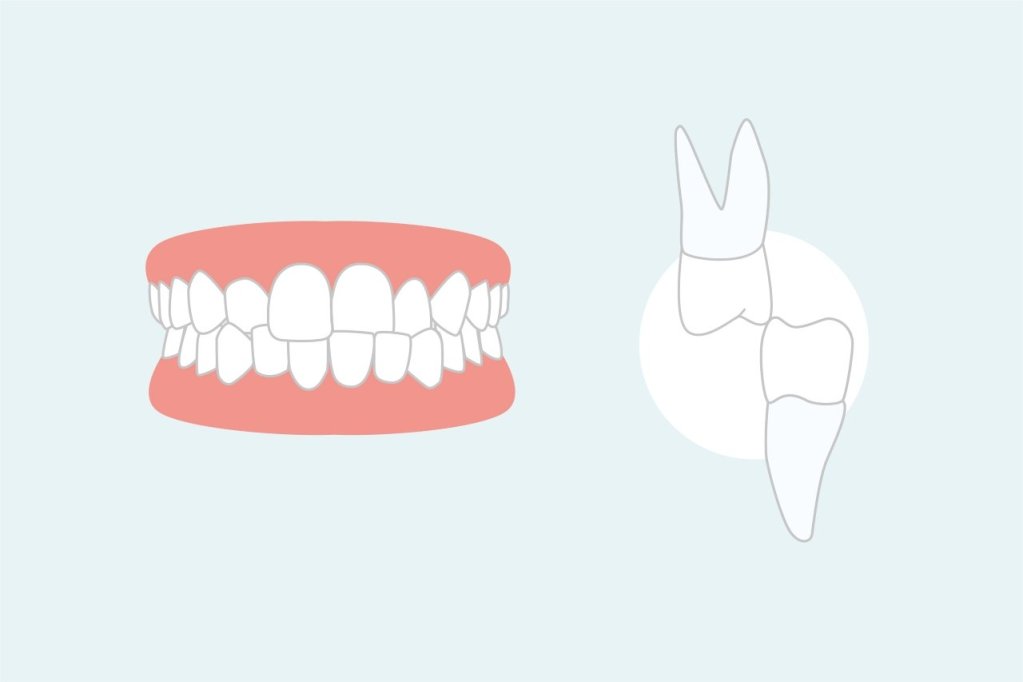

A mordida cruzada posterior ocorre quando os dentes posteriores inferiores se sobrepõem aos superiores.

Este tipo de mordida pode afetar um lado ou ambos os lados da boca.

As consequências incluem dificuldades na mastigação, assimetrias faciais e problemas na articulação temporomandibular.

O diagnóstico da mordida cruzada posterior pode ser mais sutil, exigindo um exame clínico detalhado e, em alguns casos, radiografias complementares.

Para casos de mordida cruzada posterior, os expansores palatinos são frequentemente utilizados.

Esses aparelhos ajudam a alargar o palato, corrigindo a mordida cruzada de forma progressiva.

Expansores de palato

Os expansores de palato são dispositivos usados principalmente em crianças e adolescentes para corrigir mordidas cruzadas posteriores.

Eles funcionam alargando gradualmente o palato ao longo do tempo, criando espaço para os dentes se alinharem corretamente.

O tratamento com expansores de palato é geralmente realizado antes da instalação de aparelhos fixos e pode prevenir a necessidade de intervenções mais complexas no futuro.